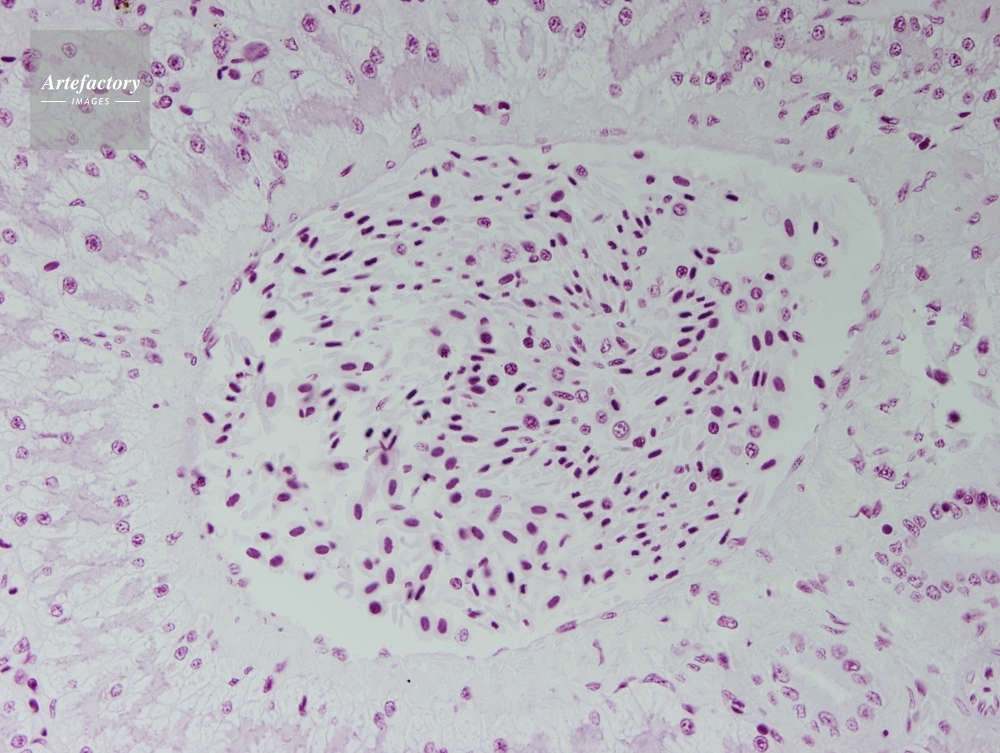

| 作品タイトル | カエル,肝臓 | モデルリリース | なし | |

| 作家 | OLYMPUS CORPORATION Technolab | プロパティリリース | なし | |